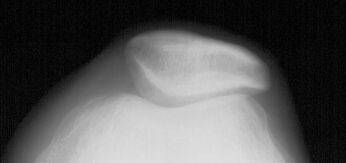

Преимущество бокового снимка, по сравнению с аксиальными проекциями, связано с возможностью анализа движения надколенника в самом начале сгибания от 0 до 30°, когда он начинает внедряться в трохлеарное устье дистального эпифиза бедренной кости. В этот момент можно оценить глубину межмыщелковой борозды и установить дисплазию трохлеи, которая может оказаться причиной нестабильности.

Измерение трохлеарного индекса производится в 1 см от верхнего края межмыщелковой поверхности, что соответствует зоне внедрения надколенника в самом начале сгибания. В норме он должен равняться 1 см (рис. 5). Индекс ниже 1 см свидетельствует о дисплазии надколенника, которая часто сочетается с недостаточным развитием суставной поверхности надколенника. При бóльших значениях индекса следует думать об излишней глубине трохлеарного устья, что увеличивает риск развития хондропатии надколенника .

Рисунок 5. Трохлеарный индекс. Объяснения в тексте.